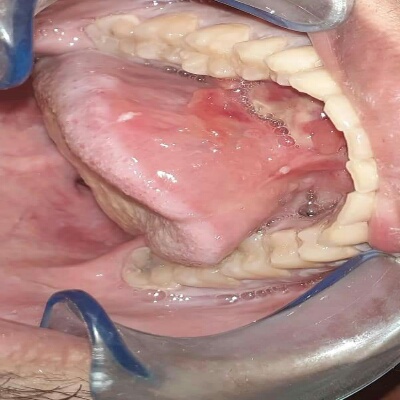

أجرى فريق الجراحة بوحدة طب وجراحة الفم والأسنان بمستشفيات جامعة بنها بقيادة الدكتور سمير حلاوة استشاري جراحة الوجه والفكين عملية استئصال حصوة بقناة الغدة اللعابية أسفل الفك من الجهة اليسرى

وقد اجريت لشاب يبلغ من العمر 27 عام تحت تأثير المخدر الموضعي حيث كان حجم الحصوة كبيرا (حوالي 1x2سم)

وقد تم ذلك بعد إجراء الفحوصات السريرية وعمل أشعة تلفزيونية ومقطعية لتحديد حجم وموقع الحصوة تفاديا لقرار استئصال كامل الغدة.